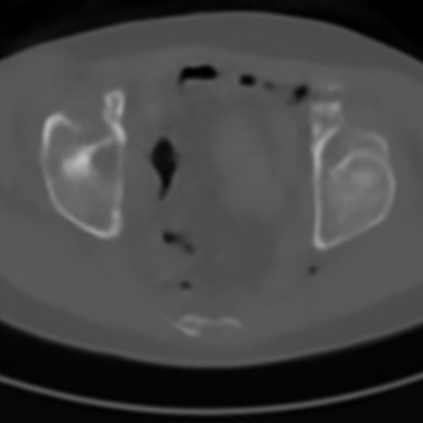

Sparse-view computed tomography (CT) -- using a small number of projections for tomographic reconstruction -- enables much lower radiation dose to patients and accelerated data acquisition. The reconstructed images, however, suffer from strong artifacts, greatly limiting their diagnostic value. Current trends for sparse-view CT turn to the raw data for better information recovery. The resultant dual-domain methods, nonetheless, suffer from secondary artifacts, especially in ultra-sparse view scenarios, and their generalization to other scanners/protocols is greatly limited. A crucial question arises: have the image post-processing methods reached the limit? Our answer is not yet. In this paper, we stick to image post-processing methods due to great flexibility and propose global representation (GloRe) distillation framework for sparse-view CT, termed GloReDi. First, we propose to learn GloRe with Fourier convolution, so each element in GloRe has an image-wide receptive field. Second, unlike methods that only use the full-view images for supervision, we propose to distill GloRe from intermediate-view reconstructed images that are readily available but not explored in previous literature. The success of GloRe distillation is attributed to two key components: representation directional distillation to align the GloRe directions, and band-pass-specific contrastive distillation to gain clinically important details. Extensive experiments demonstrate the superiority of the proposed GloReDi over the state-of-the-art methods, including dual-domain ones. The source code is available at https://github.com/longzilicart/GloReDi.